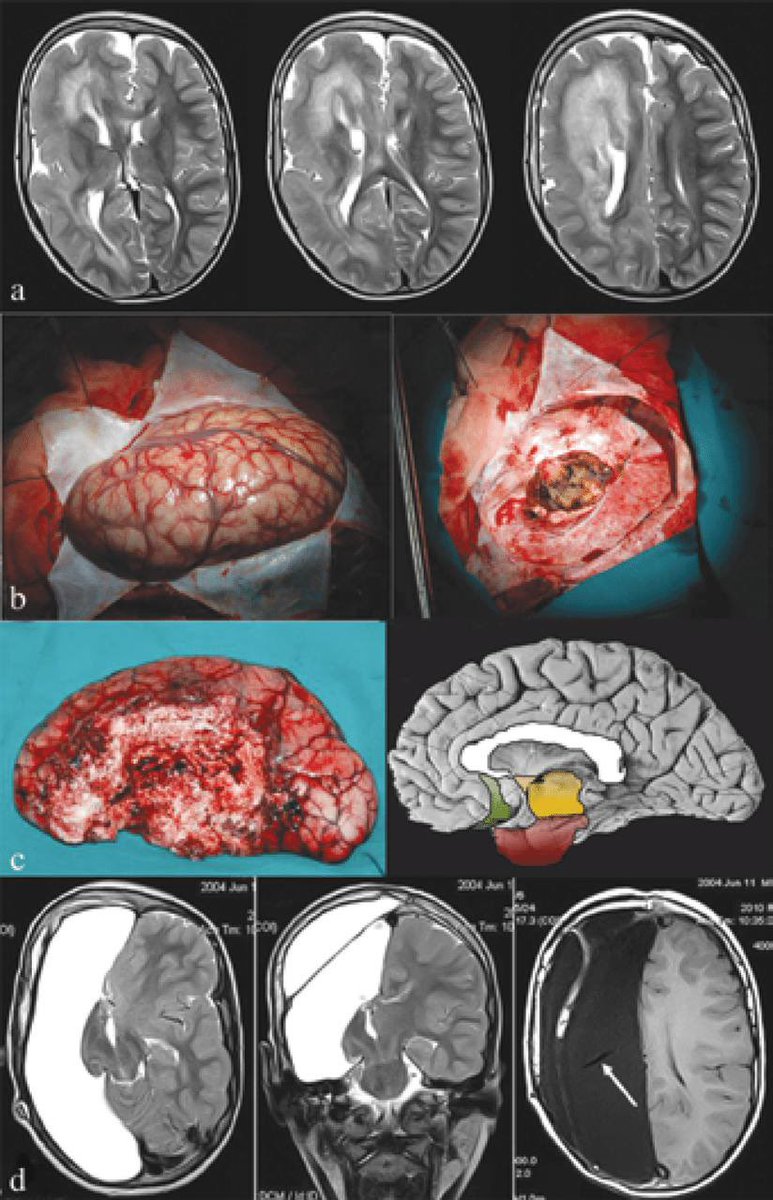

اولاً (anatomical hemispherectomy)

أو ازالة نصف المخ، وهي عبارة عن ازالة النصف المصاب تمامًا واخراجه برا الجسم.

ثانيًا (functional hemispherectomy)

أو فصل نصف المخ، واللي يعتبر تطور جدًا كبير لهذي العملية، وهو عبارة عن ازالة جزء اقل من نصف المخ المصاب خارج الجسم، مع ذلك النصف هذا مفصول تماما وظيفيًا عن نصف المخ الثاني وباقي الجسم، بالعامية كأنك فصلت السلك اللي يشبكة مع باقي الجسم.

هذا الفيديو يوضح تصوير اشعة الرنين المغناطيسي للدماغ بعد عملية استئصال نصف الكرة المخية.